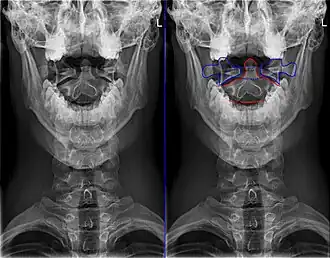

Tweede halswervel, of epistropheus bovenaanzicht | ||||